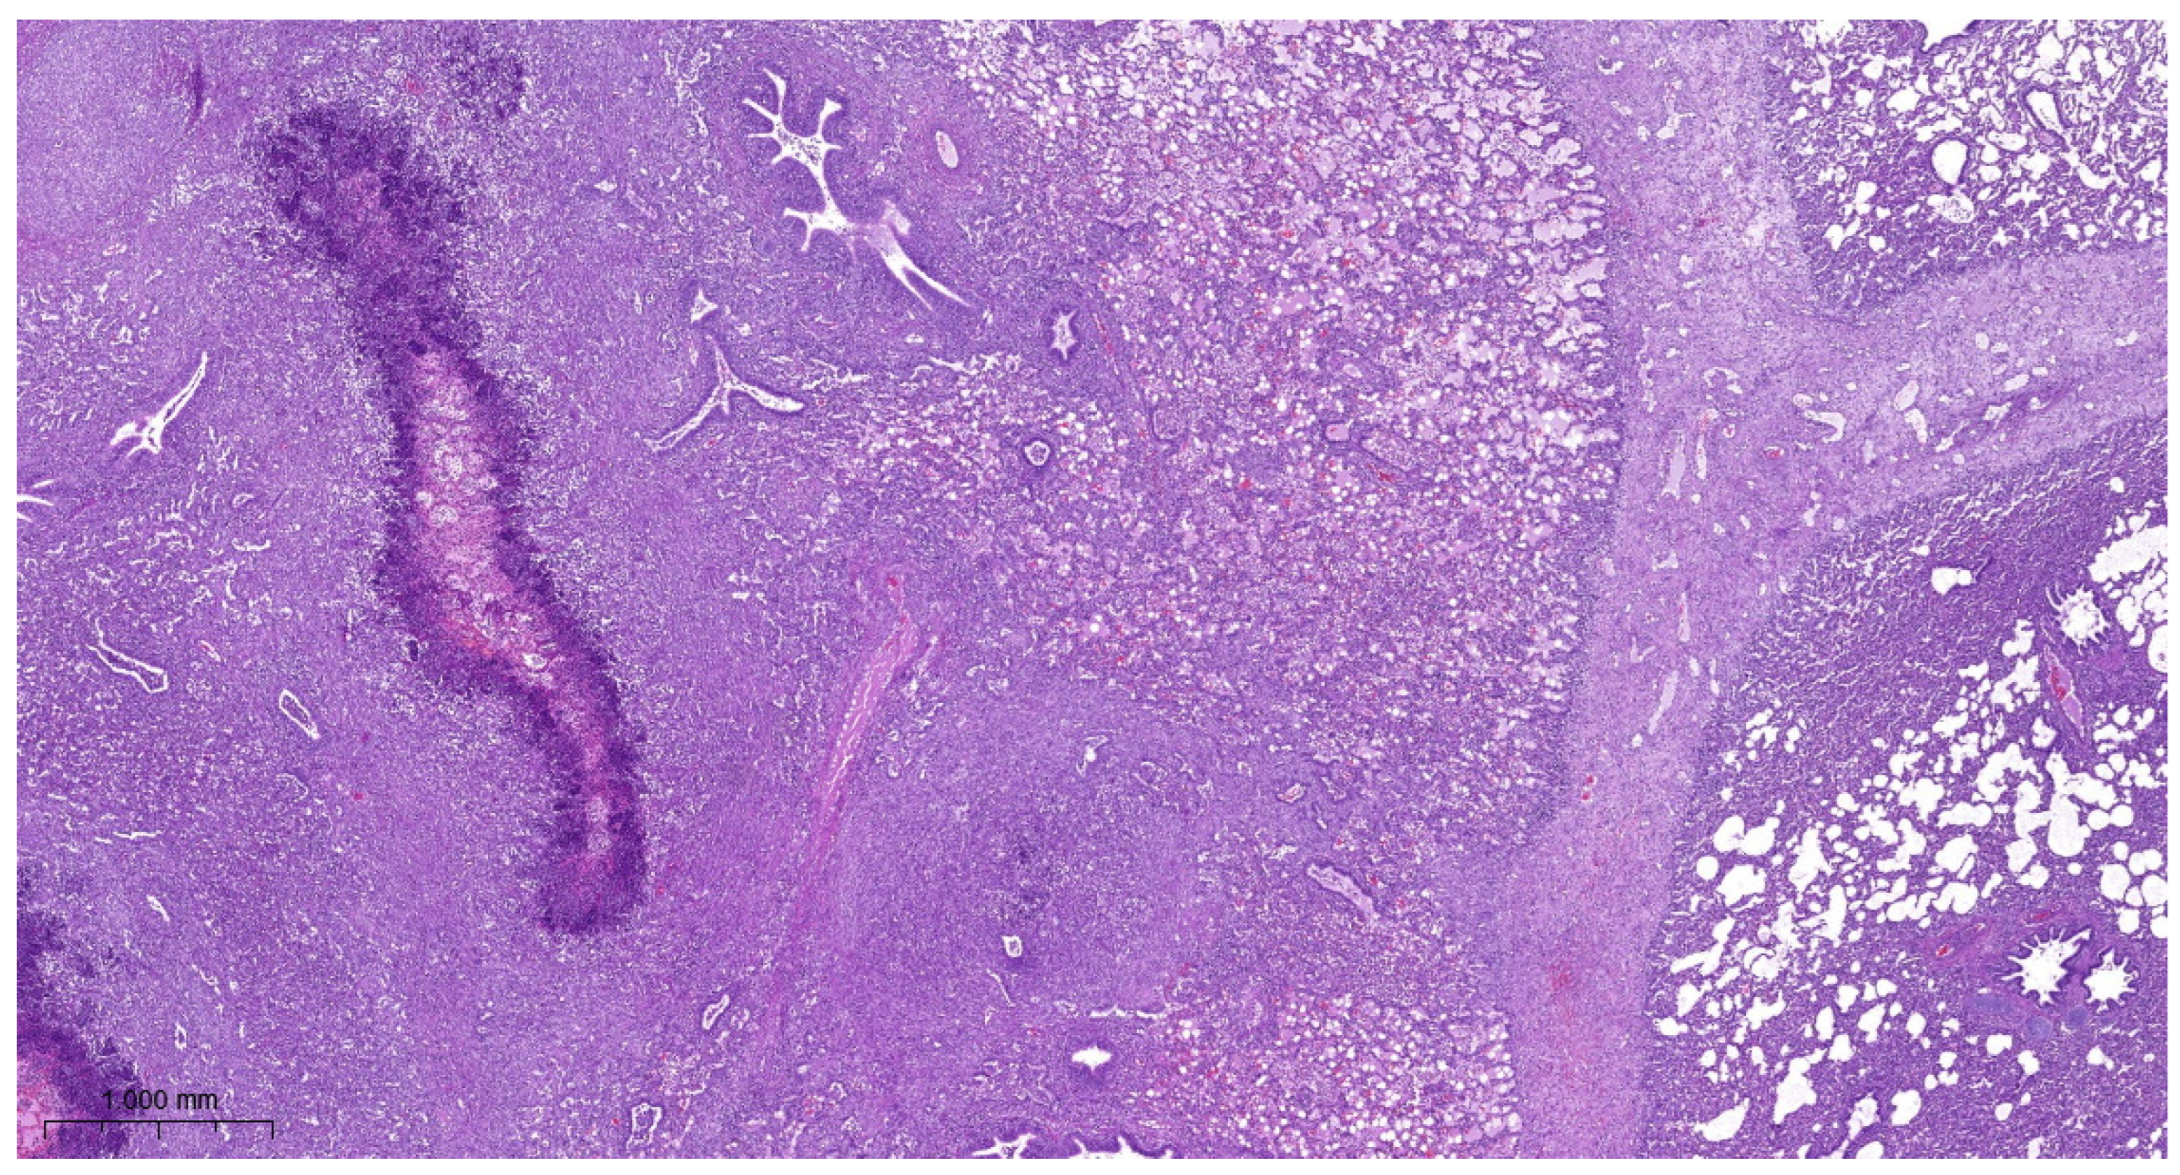

3.4. Histopathology